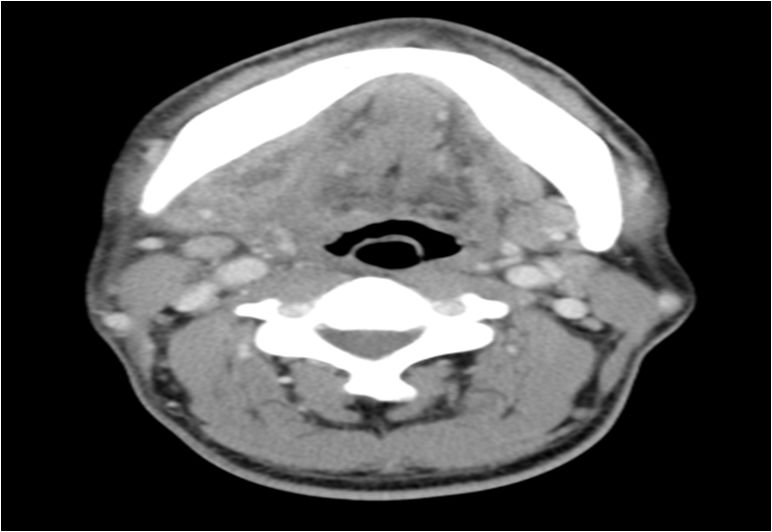

02 咀嚼肌间隙、翼下颌间隙、颊间隙

男,31岁,患者约3天前出现右侧面部口角区局限性肿胀,无明显触压痛,既往右侧下颌后牙区阵发性锐痛,曾自行口服消炎药处理,自诉牙痛症状无明显缓解,约3天前牙痛症状加重,伴夜间痛,后自觉右侧面部肿胀,约2天前开始发热,体温39.8℃。